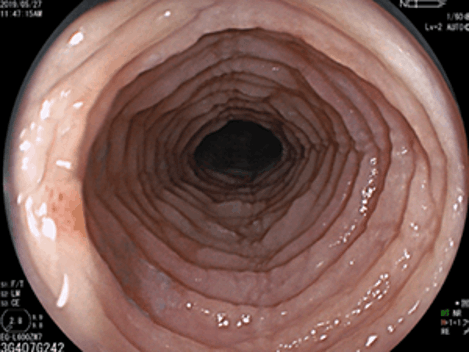

診断する上では、胃カメラ(胃内視鏡検査)が欠かせないものとなります。典型的な内視鏡像としては、食道で縦方向に長い数条の溝(縦走溝)、それと直交する何重にも渡る輪状溝(これによって食道が気管様に観察されることも)、縦走溝周囲にとくに目立つ細かい白斑となります。一方で、初期や軽症例では内視鏡的にはほとんど異常を認めないことも多いです。

縦走溝・輪状溝の見られる好酸球性食道炎

所見が強く気管様に観察されるEoEが…